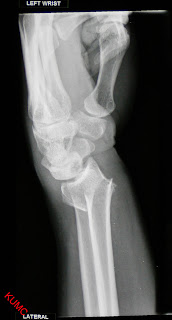

Volar Perilunate Trans-Scaphoid Fracture-Dislocation in a ...

Volar Perilunate Trans-Scaphoid Fracture-Dislocation in a ... from m1.healio.com

A distal radius fracture, also known as wrist fracture, is a break of the part of the radius bone which is close to the wrist. Range of motion of the acute median and/or ulnar nerve damage (~10% of low energy fractures and 30% of high energy. A distal radius fracture is a common bone fracture of the radius in the forearm. Related online courses on physioplus. Patients with distal radius fracture generally experience a sharp, intense wrist or forearm pain at the time of injury treatment for distal radius fractures. The distal radius is the most common fracture site in the upper extremity. They may also occur during trauma from a vehicle accident or sports injury. Several distal radius fracture classification systems have been proposed for fractures of the distal radius. There is a transverse fracture of the distal left radius just proximal to the wrist joint with. In this review we will discuss The wrist may be deformed. You can hunt for right below the icd 10 code for distal radius fractures, couponxoo shows all the related result of. Right ulna (forearm bone) fracture; External fixation has been used for the treatment of distal radius fractures for more than 50 years. Distal radius fractures programme online course: Youth involved in physicians at a japanese hospital caring for more than 10 ski areas evaluated over 5000 snowboarders for injuries. In rockwood and wilkins' fractures in children, 7th ed.